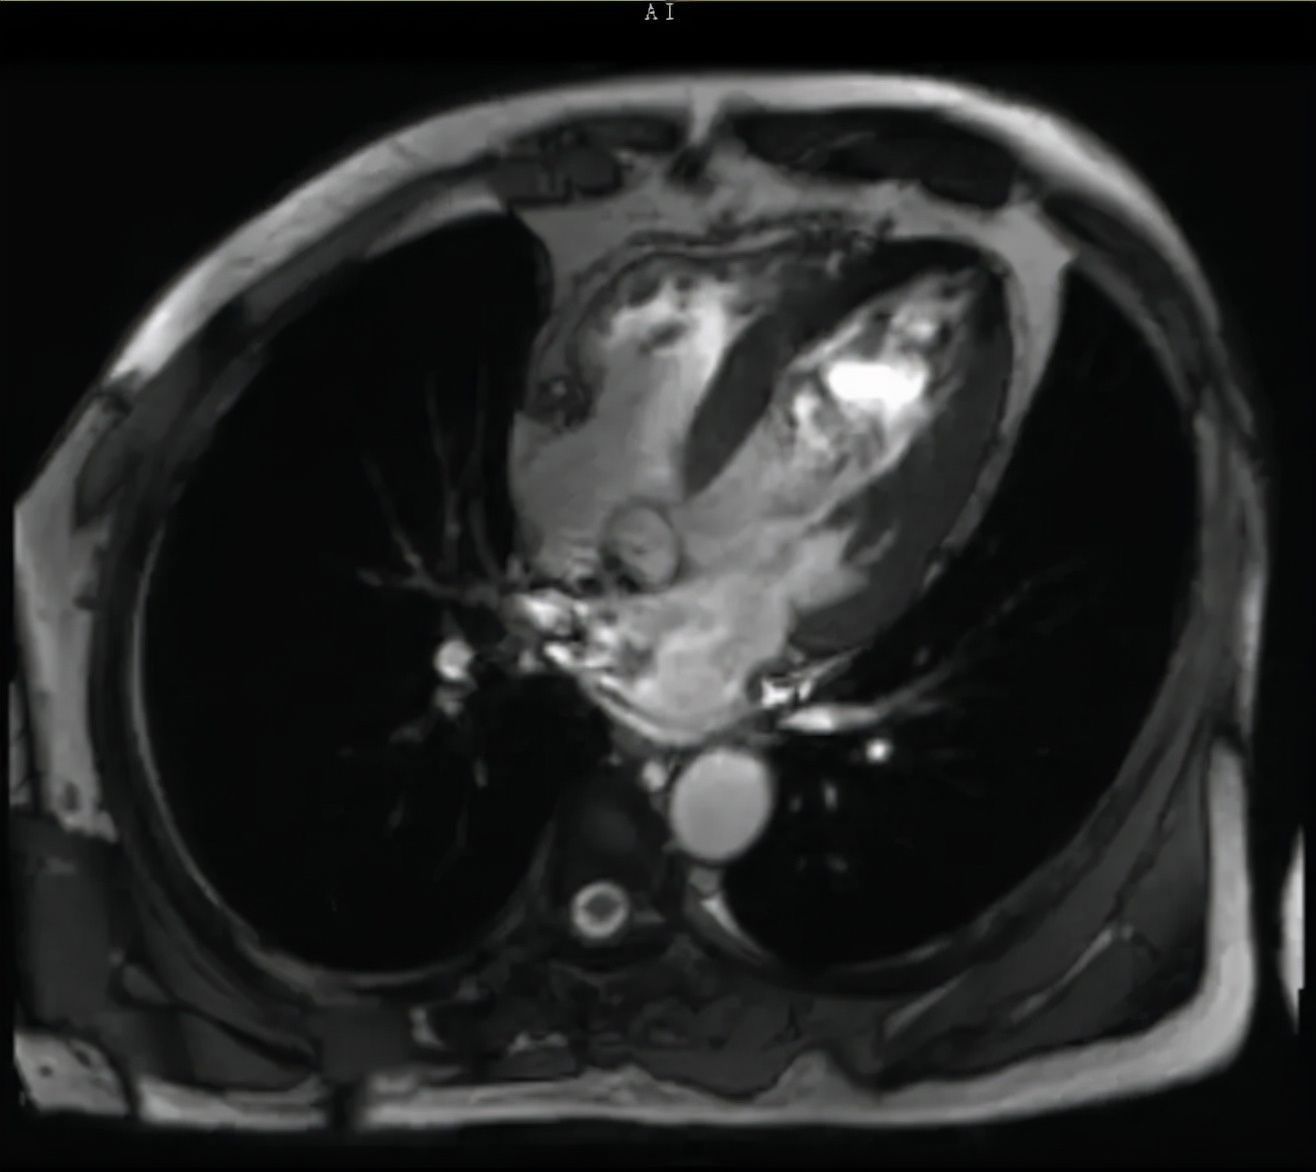

吴振垣医生给他又重新做了各项检查后发现,好家伙,血压越来越高,左心室也越长越大,整个心已经增大了一倍,心衰情况继续加重。

文章插图